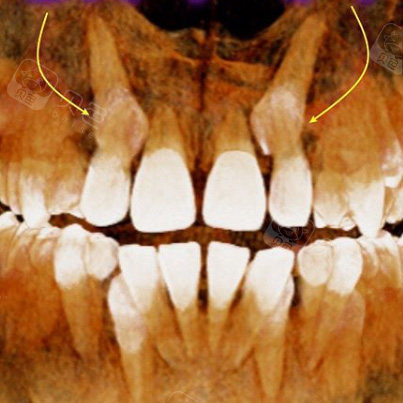

上颌高位埋伏牙,磨牙根分叉阻生一例

图片尺寸653x490